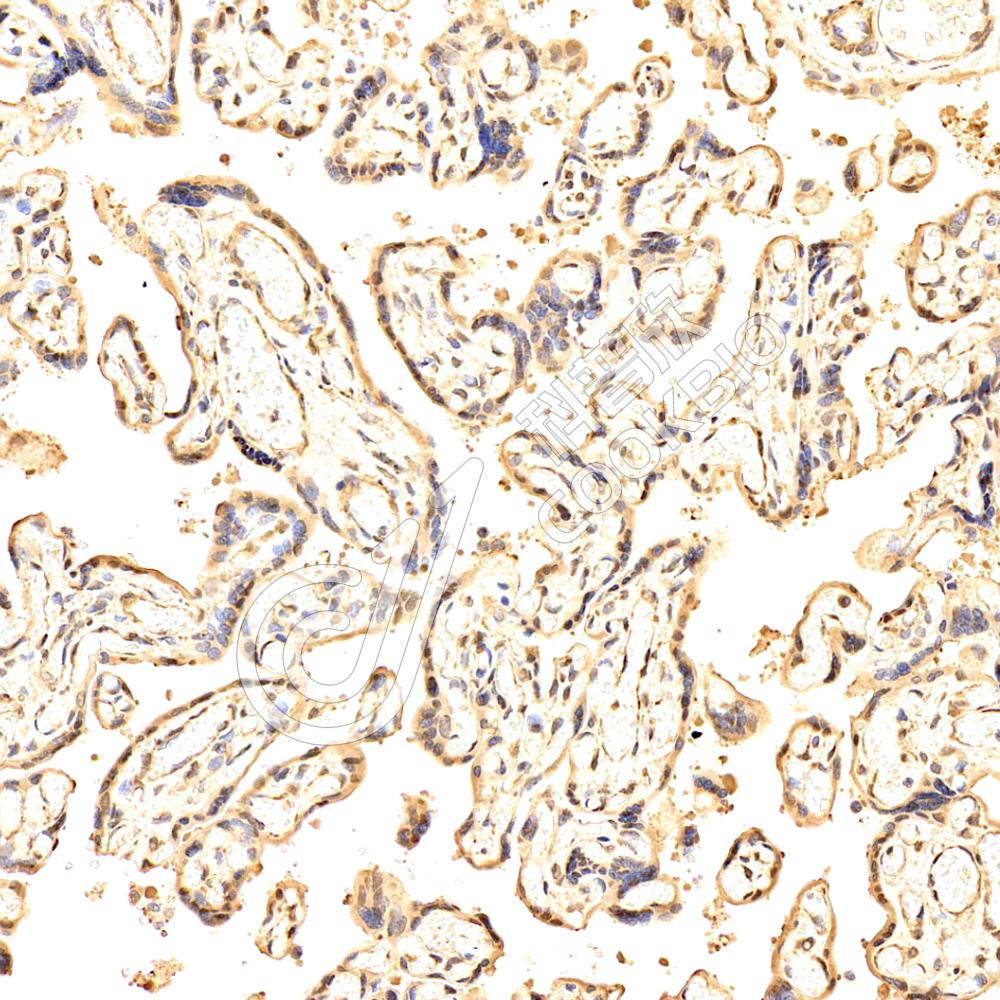

IHC检测TPPP3蛋白(货号 K1338052).

样品: 人胎盘, 4%多聚甲醛 (货号KSG1101) 固定12-24小时.

抗原修复: 柠檬酸抗原修复液(干粉, pH 6.0) (KSG1201), 98℃, 20分钟.

—抗: 1: 2300稀释, 4℃ 孵育过夜.

二抗: S-vision免疫组化多聚二抗(山羊抗兔),即用型 (货号KB3906), 室温孵育20分钟.